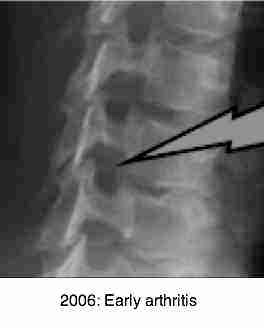

Notice the relatively minor degenerative changes in the first and third x-rays taken in 2006. The radiological report stated that there was slight loss of C5 on C6 disc space; the spinal canal had sufficient depth, and the foramina were all normal.

Notice the severe changes that have occurred in only three and a half years. I have only shown the right oblique, but the left is almost identical.

Notice the advanced degenerative changes in the unco-verebtral joints

bilaterally. The astonishingly swift development of Immobilisation Arthritis gives

testimony to the importance of normal joint nutrition and movement.